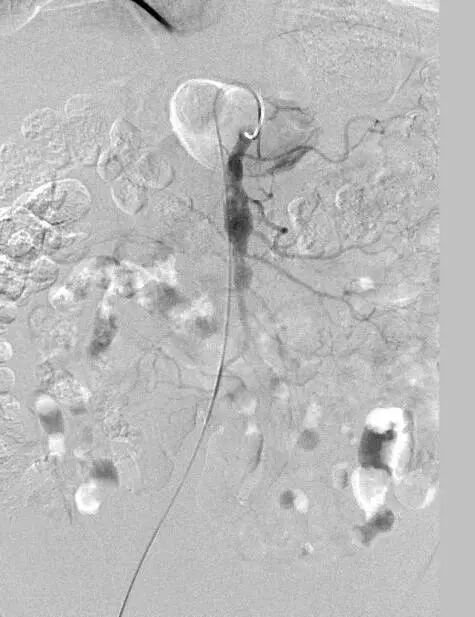

术前造影图像

患者取仰卧位,双侧腹股沟区消毒铺单后局麻下分别经双侧股动脉穿刺置入7F(右侧)/5F(左侧)血管鞘组,予40mg肝素钠静脉注射全身肝素化,先经左股动脉插入4FRH导管,将导管头端置于肠系膜上动脉开口处,注入对比剂行肠系膜上动脉IADSA;再经右侧股动脉插入7F长鞘至肠系膜上动脉开口,旁路加压滴注生理盐水;明确病情后选取工作角度,先经4FRH导管路途下同轴送入1.7F栓塞微导管,旁路加压滴注生理盐水,经微导丝配合将其头端至于肠系膜上动脉夹层囊状动脉瘤腔内,于动脉瘤填入5枚弹簧圈行夹层动脉瘤弹簧圈填塞术;经右侧股动脉长鞘入路沿导丝送入1枚支架(SmartFlex 6mm×80mm,USA)该支架具有可预见的近端定位+参考Marker,准确定位后行肠系膜上动脉真腔成形术,支架覆盖夹层段。复行肠系膜上动脉IADSA示:支架位于肠系膜上动脉主干夹层段,支架覆盖夹层动脉瘤出入破口,支架内血流通畅,分支血管显影良好,支架以远血管主干及分支显影较术前增多增浓,多发夹层动脉瘤腔内弹簧圈均匀填塞。手术结束,使用Exoseal封堵止血系统闭合双侧股动脉穿刺点。